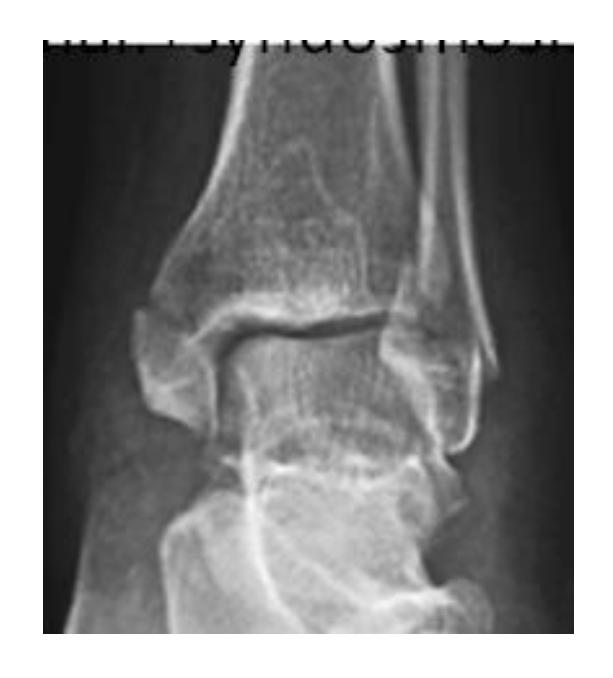

Ankle and Distal Lower Leg

Syndesmotic Injuries

A 17-year-old male had a high ankle sprain followed by pain in his leg. X-ray films were obtained. According to the attached X-ray, which structure has been injured?

- B. Syndesmosis ligament

A 23-year-old male injured his ankle after a twisting ankle injury 2 days back. What is the most likely pathology based on shown x-ray?

Management Question: What is the management of the finding in the image?

- A. Screw fixation for syndesmosis injury

Mortise View of the Ankle